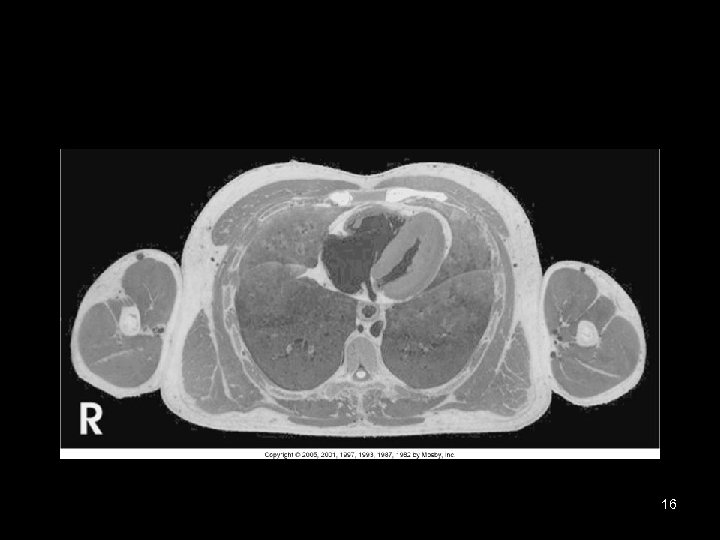

16